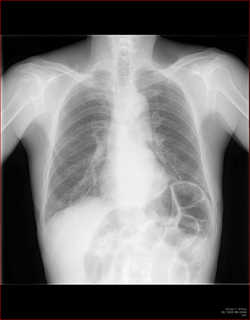

B正面像で見えるリンパ節

傍気管線、A-P window、気管分岐部は必ずチェックしましょう。

C縦隔や横隔膜の動きを見る

これらの動きから、肺容量の増減がわかります。